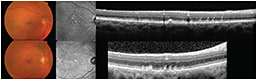

The first commercially available OCT systems were based on so-called time-domain technology. In time-domain OCT, a mechanical moving part performed the A-scan, and the information along the longitudinal direction accumulated over the course of the longitudinal scan time. These systems performed 400 axial scans per second and had an axial resolution of 8-10 µm (Figure 1A).

Figure 1. A) Time-domain OCT (Stratus OCT; Carl Zeiss Meditec, Dublin, CA); B) Spectral-domain OCT (Spectralis, Heidelberg Engineering, Carlsbad, CA).

In contrast, modern SD-OCT systems do not have mechanically moving parts but implement the mathematical principle of Fourier transformation, measuring all echoes of light simultaneously, compared with sequentially in the case of TD-OCT

As a result, SD-OCT can perform 100,000 to 250,000 axial scans per second, with an axial resolution of 1-5 µm (Figure 1B). SD-OCT has led to faster acquisition times, facilitating the implementation of real-time eye motion tracking and B-scan averaging.